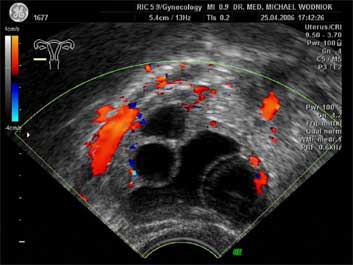

Ultraschall des kleinen Beckens mit der Vaginalsonde Die Ultraschalluntersuchung ist ein bildgebendes Verfahren, welches die Reflektion oder Echos von Ultraschallwellen in den unterschiedlichen Geweben und Organen ausnützt um computergestützt Schnittbilder aus dem Inneren des Körpers zu erstellen. Durch moderne hochleistungsfähige Mikroprozessoren ist es in den letzten Jahren möglich geworden, auch 3-dimensionale oder sogar bewegte 3-dimensionale (4-D) Bilder bzw. Bildsequenzen zu erzeugen. Beides können wir Ihnen in der Praxis anbieten. Eine Ultraschalluntersuchung ist ungefährlich und schmerzfrei. Durch die Anwendung von Dopplerverfahren, mit welchen wir den Blutfluss in den Organen feststellen und messen können, erweitern wir die Untersuchung um die funktionelle Dimension. Ein weiterer Bestandteil unseres Leistungsspektrums ist die farbkodierte Dopplersonographie. Farbkodiert sind entweder die Richtung des Blutflusses oder dessen Intensität. Über die computergestütze Berechnung des Blutflusswiderstandes ist im Einzelnen eine Aussage bzw. Vorhersage über die qualitative und quantitative Durchblutung möglich. (Plazentadurchblutung, kindliche Blutgefässe, Durchblutungsmuster bei verschiedenen Tumoren des Unterleibes und der Brustdrüsen) Ultraschalluntersuchungen haben in unserem Fachgebiet vielfältige Anwendungsmöglichkeiten gefunden. Besonders faszinierend ist der Einsatz im Bereich der vorgeburtlichen Diagnostik. Bereits in der 10. Schwangerschaftswoche ist es möglich, die Extremitäten des Embryos darzustellen und Aussagen zum Körperumrissbild zu machen (Ausschluss von Spaltbildungen, Nackentransparenzmessung). Auch im Bereich der Gynäkologie ist die Bedeutung des Ultraschalls stetig gewachsen und hat sich als erweiterte Vorsorge etabliert. Durch die vaginale Ultraschalluntersuchung können bereits kleine Veränderungen entdeckt werden, die sich der manuellen Tastuntersuchung noch entziehen. Auffällige Tastbefunde an den Eierstöcken sind durch den Einsatz von 3D / 4D in Kombination mit der Farbdoppleruntersuchung besser interpretierbar und können dadurch Frauen unnötige abklärende Operation ersparen. Die Anwendung des 3D Ultraschall, insbesondere im Coronarschnitt, lässt eine effektive Beurteilung für Veränderungen (Polypen, Karzinome) der Gebärmutterschleimhaut zu. ![]() ![]() ![]() ![]() ![]() |